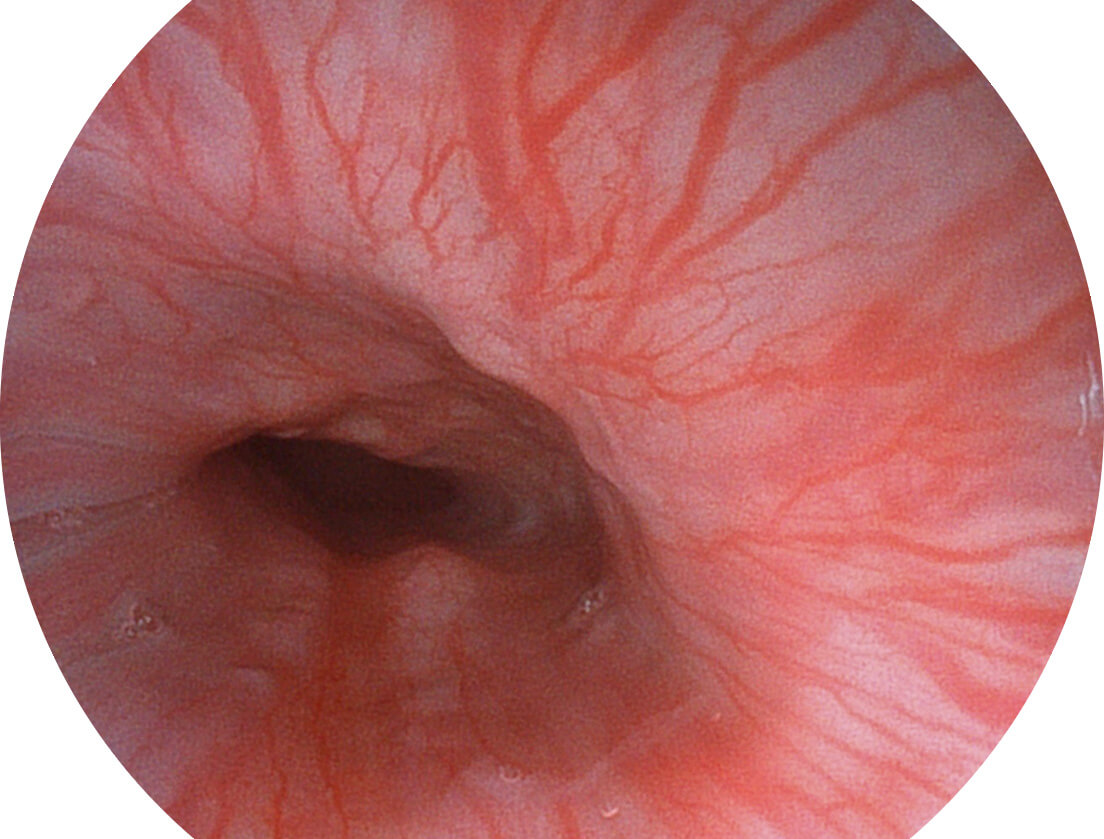

白光图像

SFI图像

图像具有高亮度、高黏膜血管颜色对比度的特点,且不改变粘液、食物残渣、粪便的基本颜色,可在中远景下进行观察,助力消化道早期疾病的诊断。